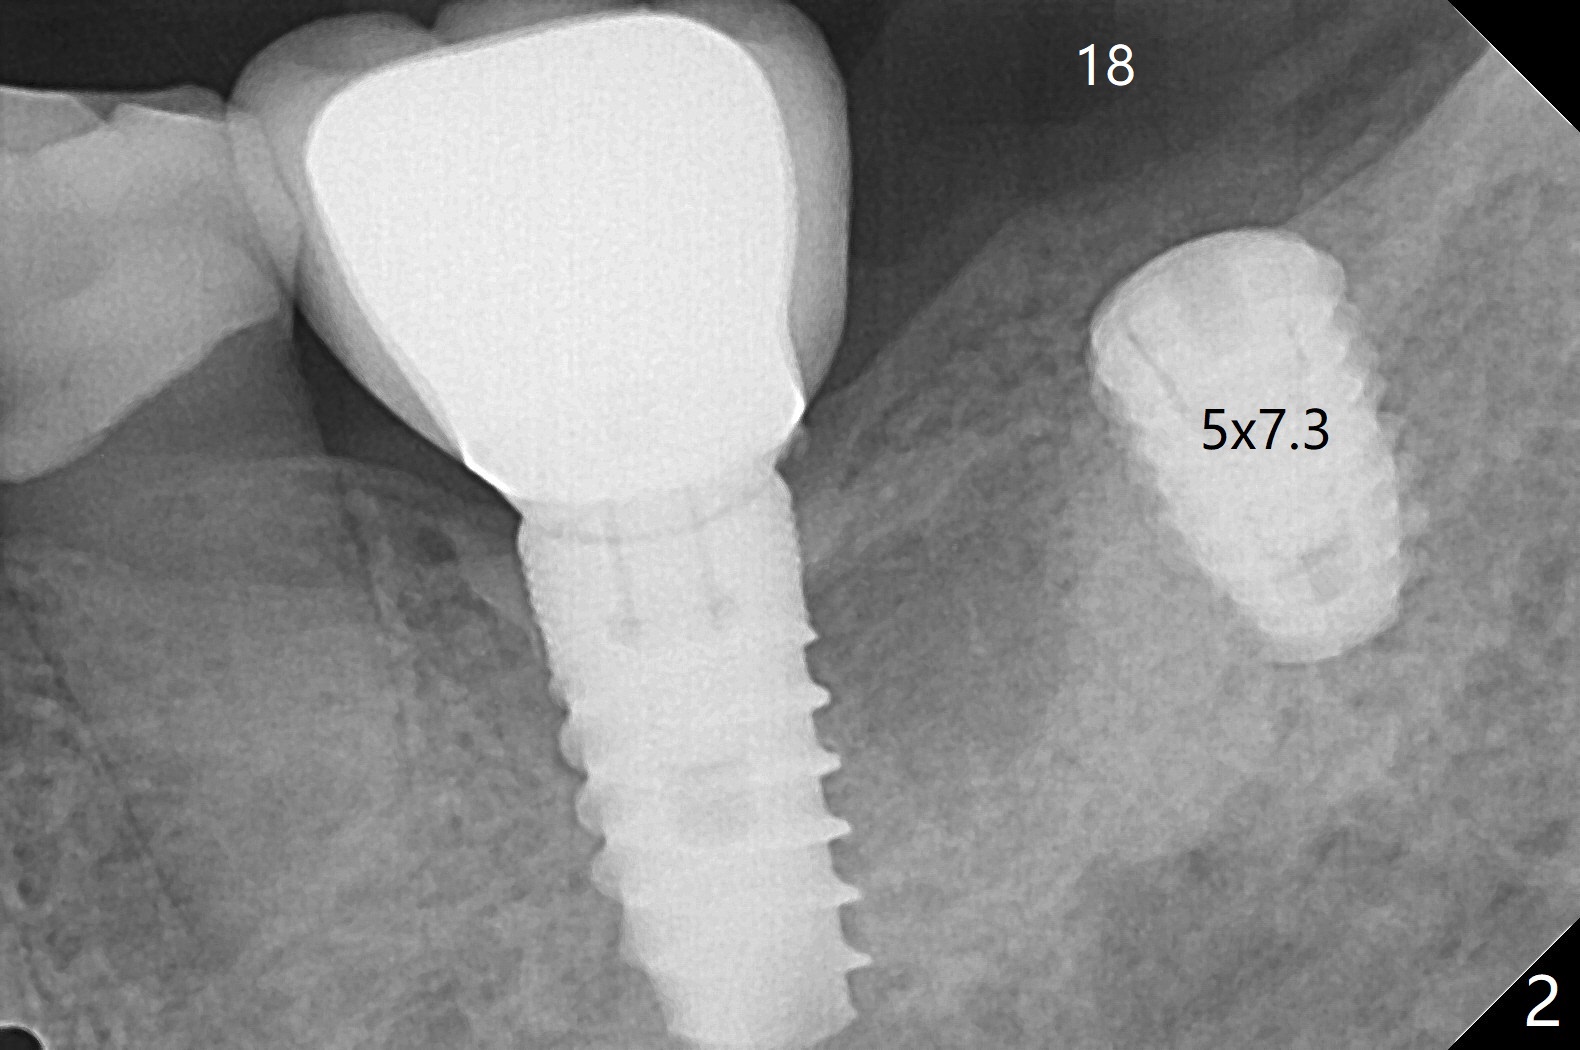

Biopsy punch is used after guide tissue punch marking at #15 because of expected low stability associated with a 8.5 mm long implant for the 73-year-old woman (Fig.1). For #18 site, the same punch is reused with reduced sharpness and some trauma to the tissue. After implant placement (Fig.2), the osteotomy appears to invade the buccal nonkeratinized gingiva. The saved tissue returns to the sites with perio glue fixation and perio dressing. The dressing at #18 is loose 2 weeks postop. When it is removed, the wound seems to be healing (Fig.3). The dressing at #15 remains stable 2 weeks postop (not removed).